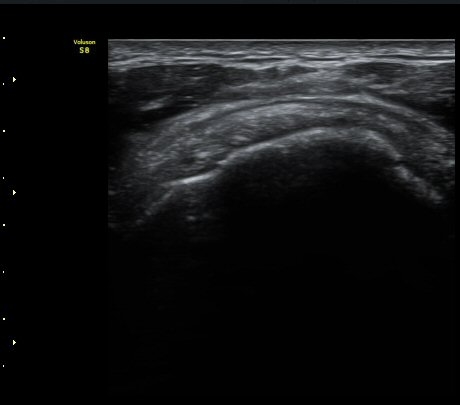

±Ø»ó°Ç Á¾´Ü¸é°Ë»ç¿¡¼­ ±Ø»ó°Ç ÆÄ¿­Àº º¸ÀÌÁö ¾ÊÀ¸³ª »ó¿Ï°ñ ´ë°áÀý°ú °ñµÎ ÀÌÇàºÎÀ§¿¡¼­

ÇÇÁú°ñ ¿¬°á ¼Ò½Ç°ú ¹Ì¼¼ÇÑ °ñÆíÀÌ °üÂûµÊ(»çÁø 3, 4, 5).